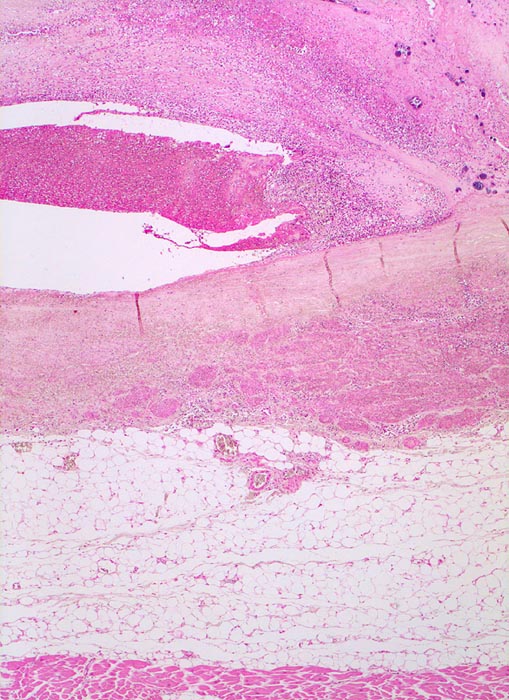

Makroskopisch sind entweder flache rötliche fibrinbelegte Ulzera (=ulcerosa (> 2935)) oder zusätzlich weiche gelbbraune bröcklige erbs- bis pflaumengrosse Polypen (=ulceropolyposa (> 2936) (> 8376)) oder ausschliesslich polypoide Fibrinbeläge (=marantica) auf einem Endokarddefekt oder einer partiell zerstörten Klappe erkennbar.

Histologisch findet sich bei ulzeropolypöser Endokarditis ein Fibrin-Thrombozytenthrombus, welcher von Bakterien durchsetzt ist (=Vegetation). Die Vegetation sitzt auf einem Klappendefekt an dessen Basis Granulationsgewebe einzusprossen beginnt, welches den Thrombus organisiert. Klappendefekte, Gefässeinsprossungen, verdickte Sehnenfäden (> 2848) oder Kommissurenverwachsungen (> 8389) der Taschenklappen weisen morphologisch auf eine abgeheilte Endokarditis hin.

• Längsschnitt durch Aorta, Aortenklappe und linkes Ventrikelmyokard.

• Oben im Bild die Aorta mit kleinem Fibroatherom.

• Abszedierende Entzündung der aortalen Adventitia ausgehend von septikopyämischen Streuherden.

• Ulzerierte Aortenklappe(ulcerosa).

• Dem ulzerierten Klappengerüst aufgelagerte polypöse Vegetation aus Fibrin und Granulozyten durchsetzt von blauen Kokkenbakterienkolonien (polyposa).

• Ausgedehnte frische Koagulationsnekrose (unsichtbare Zellkerne, Infiltrate neutrophiler Granulozyten) des linken Ventrikelmyokards unterhalb der Klappe.